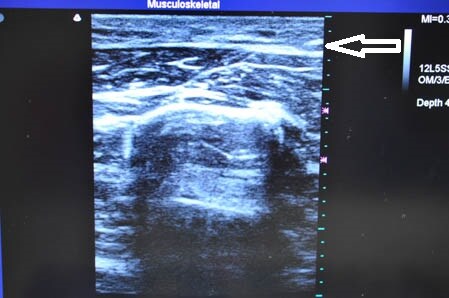

右二の腕。

↓ ↓ ↓

左二の腕。